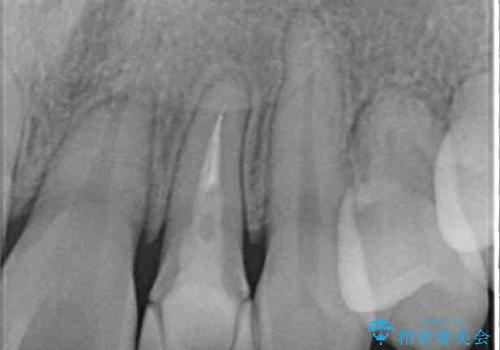

- 下顎の歯が舌側に倒れていることと、前歯の咬み合わせの不具合を気にして来院された患者様です。

前歯には治療中の仮歯が装着されていたため、矯正治療後にオールセラミッククラウンにて補綴治療を行うこととしました。